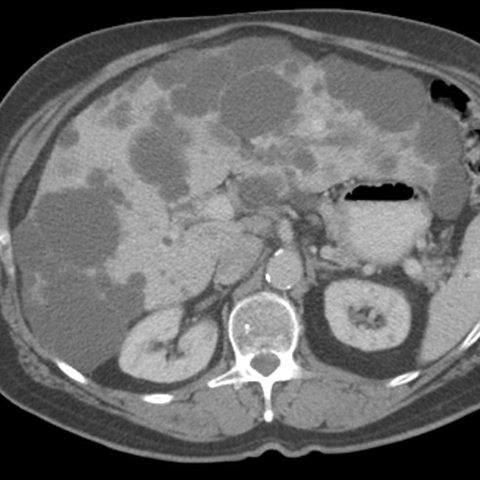

46 year-old male presents with increasing abdominal girth. [2 of 2]